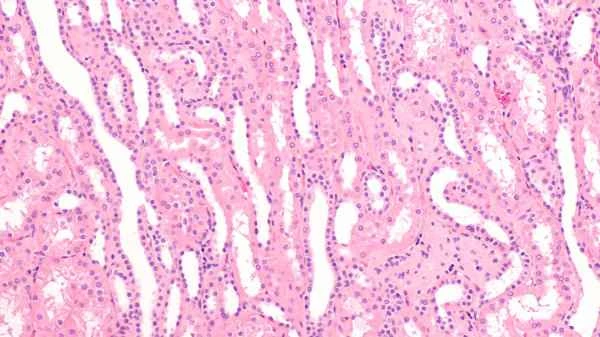

Sigmoid colon leiomyomas are tumors that occur in the sigmoid colon and are composed of smooth muscle cells. These tumors typically do not spread to other parts of the body and are not invasive, therefore they are mostly benign. However, even so, regular medical checkups are still necessary to ensure that the tumor has not changed. Through endoscopy, imaging examinations, and other methods, doctors can accurately determine the nature and size of the tumor, thereby developing the most suitable treatment plan for the patient.